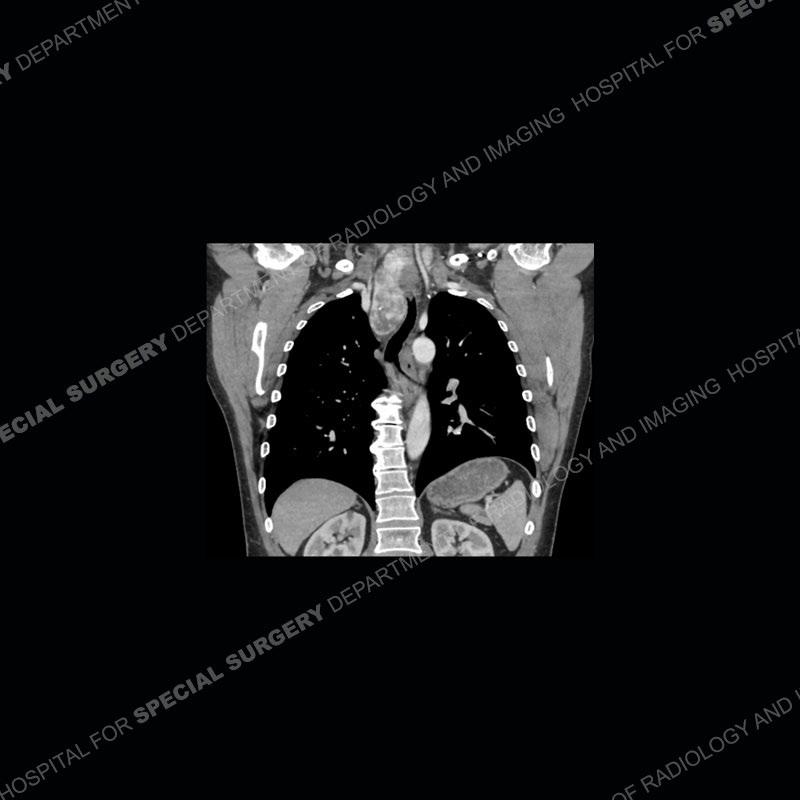

Findings

The chest radiographs demonstrate a leftward deviation of the trachea. CT images demonstrate a large, somewhat heterogeneous mass of the thyroid that extends outside the confines of the thyroid tissue. There is a subtle, enhancing soft tissue mass of the proximal right humerus. Slightly prominent mediastinal lymph nodes are present with additionally, multiple supraclavicular lymph nodes.

Over the years we have shown a couple of these cases which may be considered more so an “eye test” then anything else. In clinical practice, these are often very difficult cases as the initial finding of the tracheal deviation may be easily overlooked. Screening radiographs are clearly most often used to assess cardiopulmonary function before induction of anesthesia but at times other findings of great and unfortunately grave consequence can be found. The evaluation of the incidental thyroid mass on CT and MRI is an ever changing situation. Parameters such as age of patient, extension outside of the thyroid, enhancing nodules, and local invasion of lymph nodes are evaluated to see if a lesion needs to be further evaluated.

Although not strictly a part of the evaluation of an “incidental” thyroid lesion, evaluation of the adjacent lymph nodes and bony structures can also be quite important. In this case, there is an enhancing mass of the right humerus. This is very subtle and can only really be recognized by evaluating the density of the bone. Typicaly marrow will have a fatty density or nearly fluid density. As the density, as in this case, approaches soft tissue an infiltrative process must be entertained. Thyroid mets are markedly vascular accounting for the areas of enhancement of the humeral mass. The mediastinal and supraclavicular lymph nodes although not individually enlarged, should raise suspicion of an underlying inflammatory/neoplastic process.